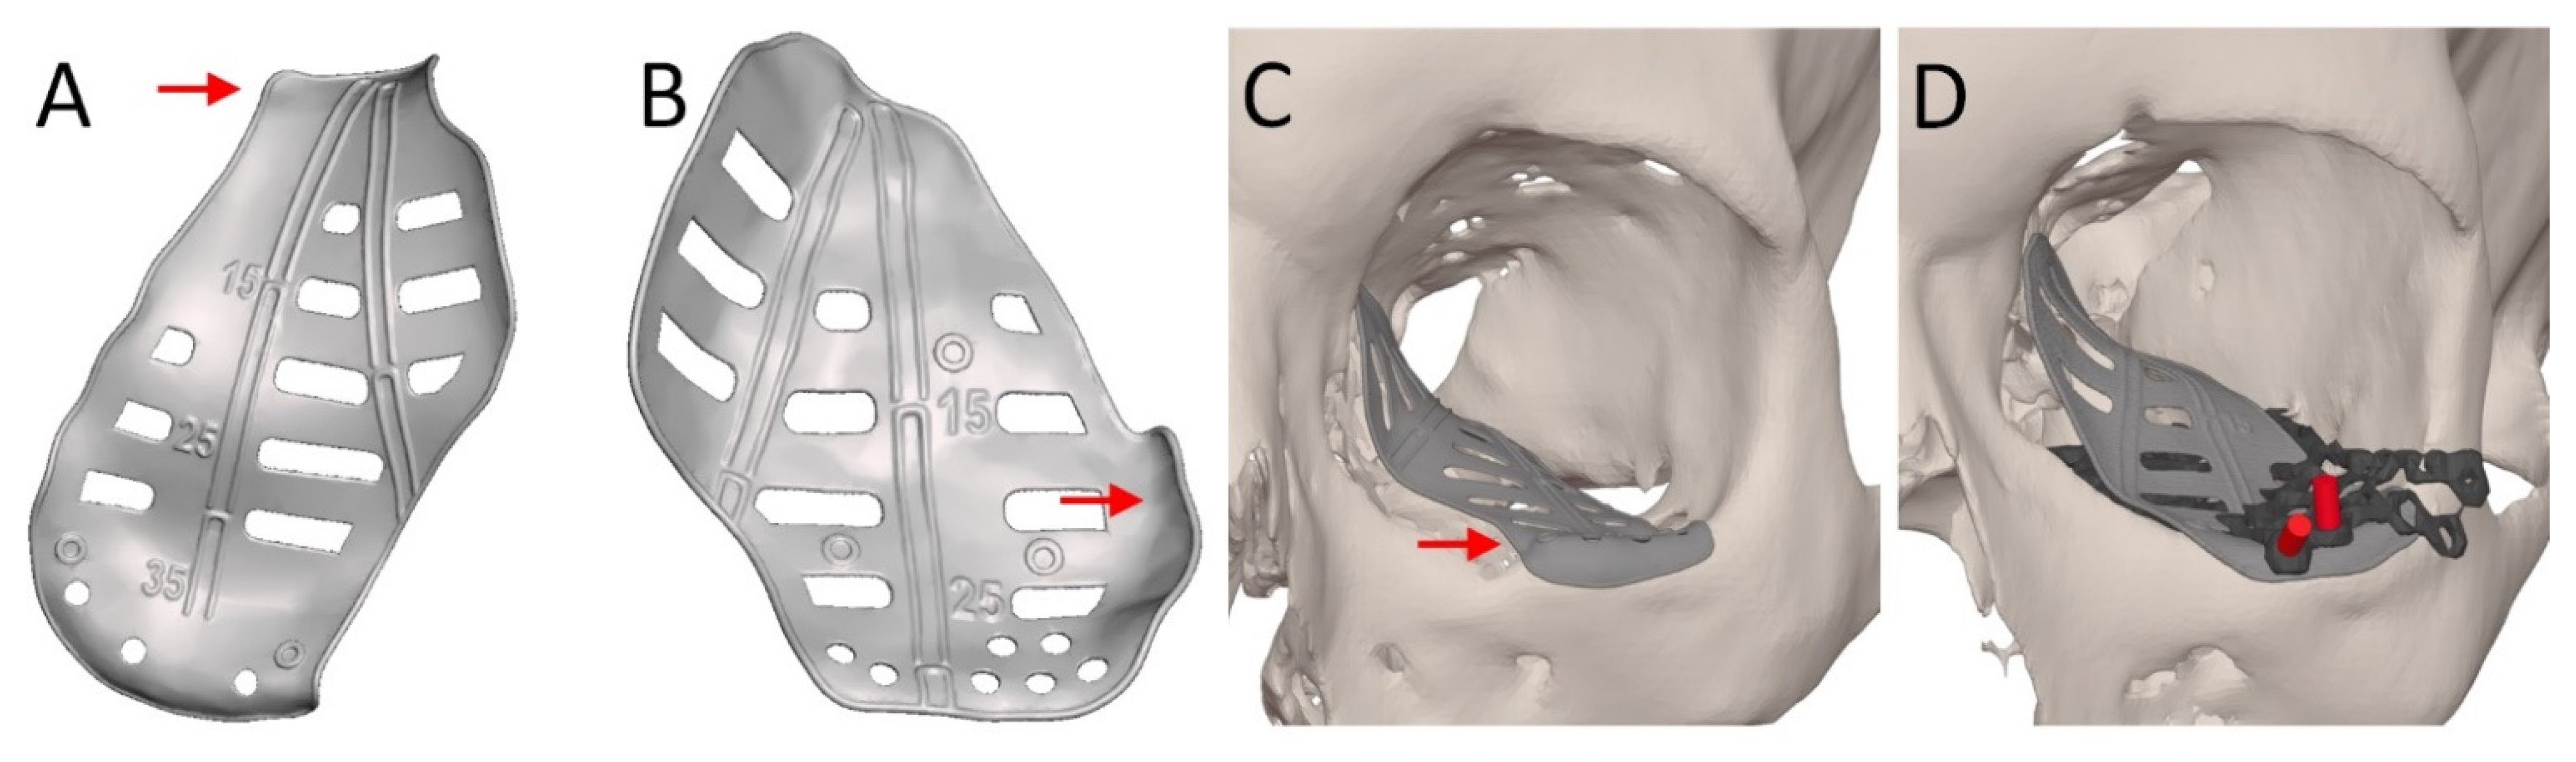

| Design Consideration | Effect on | Options | References | Notes |

|---|---|---|---|---|

| Thickness | Positioning, stability | 0.3 mm | [22,37,38] | |

| Atraumatic cord | Positioning, stability | Present | [37,39,40] | |

| Absent | [38,41,42] | |||

| Grid | Clinical symptoms | Horizontal | [22,37,40,43] | |

| Squares | [38,39,41,44] | |||

| Porous | [42,45,46] | |||

| Support | Stability, accuracy | Three points | [22] | Infraorbital rim, medial wall, posterior ledge |

| [38] | Anteromedial, anterolateral, posterior | |||

| Ledge | [37,40,43] | Inverted shovel design | ||

| Lateral posterior wall | [43] | Stabilizer for self-centering implant | ||

| Extension | Accuracy | Orbital rim | [22,42,44,46,47,48] | |

| Lateral posterior wall | [43] | |||

| Specific bone features | [45] | |||

| Anterior elevation | Clinical symptoms | [22] | Rim elevation to correct hypoglobus | |

| Overcorrection | Clinical symptoms | Location | [22] | Posterior to bulbus |

| [49] | Orbital floor elevated in sagittal relation | |||

| Amount | [22] | Based on clinical findings, advanced diagnostics | ||

| [38] | Slight overcorrection | |||

| [50] | Same amount in cubic cm as mm enophthalmos | |||

| Intraoperatively | [51] | Spacers | ||

| Navigation | Accuracy | Markers | [22,37,38,39,52] | Eminence lacrimal foramen [38] |

| Vectors | [37,40,43] | |||

| Fixation | Stability | Absent | [38,44,48] | |

| Present | [22,37,39,40,42,46,47,53] | Eccentric screw alters implant position [47] Fix implant if form stable [40] | ||

| Fixation re-use | Accuracy | Re–used screw hole | [54] | Only in secondary reconstruction |

| Multi-piece | Positioning, stability, | Lazy-S | [42,47,49] | |

| accuracy | Interlocking | [46,48,55,56] |